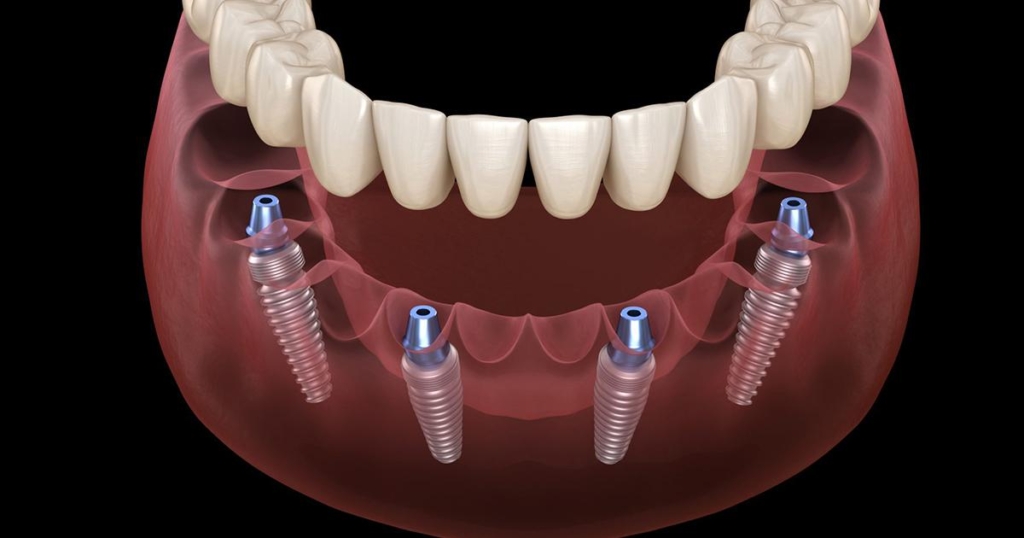

| RapidFixt 4 impianti tedeschi K3Pro + estrazione + 10-12 denti provvisori | 50000 lei |

| RapidFixt 6 impianti tedeschi K3Pro + estrazione + 10-12 denti provvisori | 70000 lei |